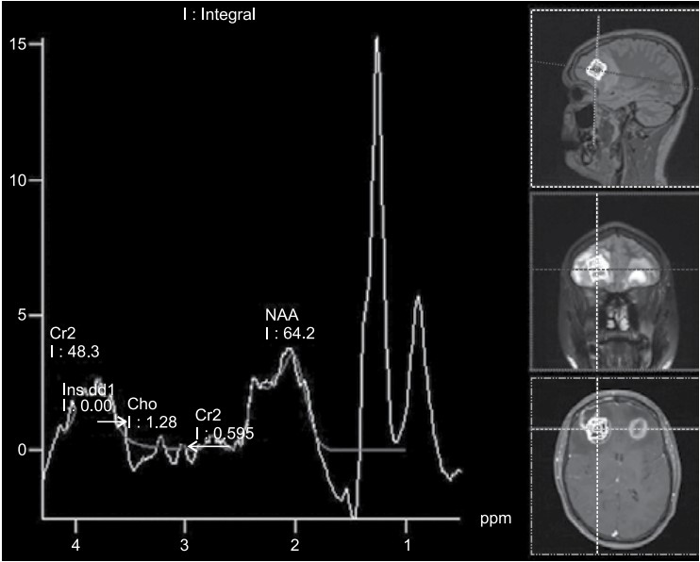

Considere o caso clínico a seguir para responder à questão.

Paciente do sexo masculino, de 23 anos de idade, vem ao pronto-socorro com queixa de cefaleia e leve confusão mental com início há 7 dias.

O paciente realizou espectroscopia de prótons apresentada a seguir:

(Arquivo pessoal; imagem usada com autorização)

Assinale a alternativa correta em relação aos achados dessa sequência de espectroscopia de prótons e o caso clínico exposto.